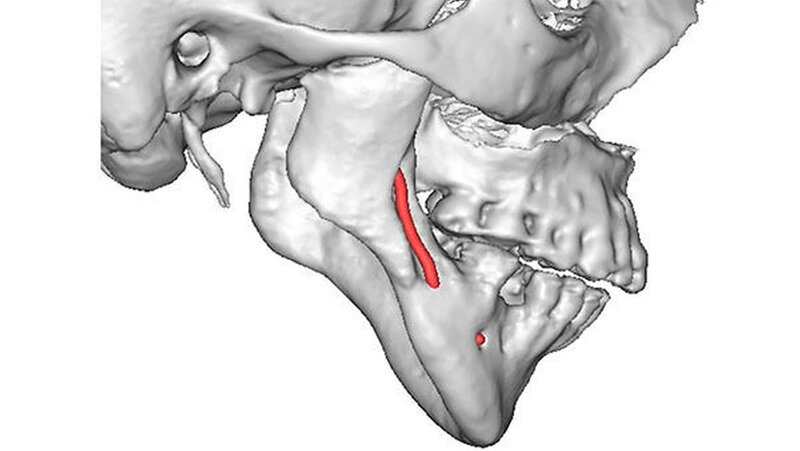

Das Bonner MKG-Chirurgenteam um Prof. Dr. Dr. Rudolf Reich diagnostizierte eine zunehmende Einschmelzung (Resorption) der Kiefergelenkfortsätze, wodurch die gesamte Abstützung des Unterkiefers am Schädel verloren gegangen war.

Mit der virtuellen Planung, individuellen Kiefergelenkprothesen und einer zusätzlichen Rückpositionierung des Oberkiefers in die ursprüngliche Lage erfolgte dann die Operation. Alles erfolgte in einem Operationsgang. Die Bonner MKG-Chirurgen fertigten die Endoprothesen für die Frau individuell im CAD-/CAM-Verfahren an. Dafür wurden die Daten der Computertomografie des Schädels zugrunde gelegt.

Durch diese hoch anspruchsvollen Verfahren ließ sich annähernd die ursprüngliche Position des Unterkiefers vor der Einschmelzung wiederherstellen; in der gleichen Operation wurde die Position des Oberkiefers der jetzt idealen Stellung des Unterkiefers angepasst.